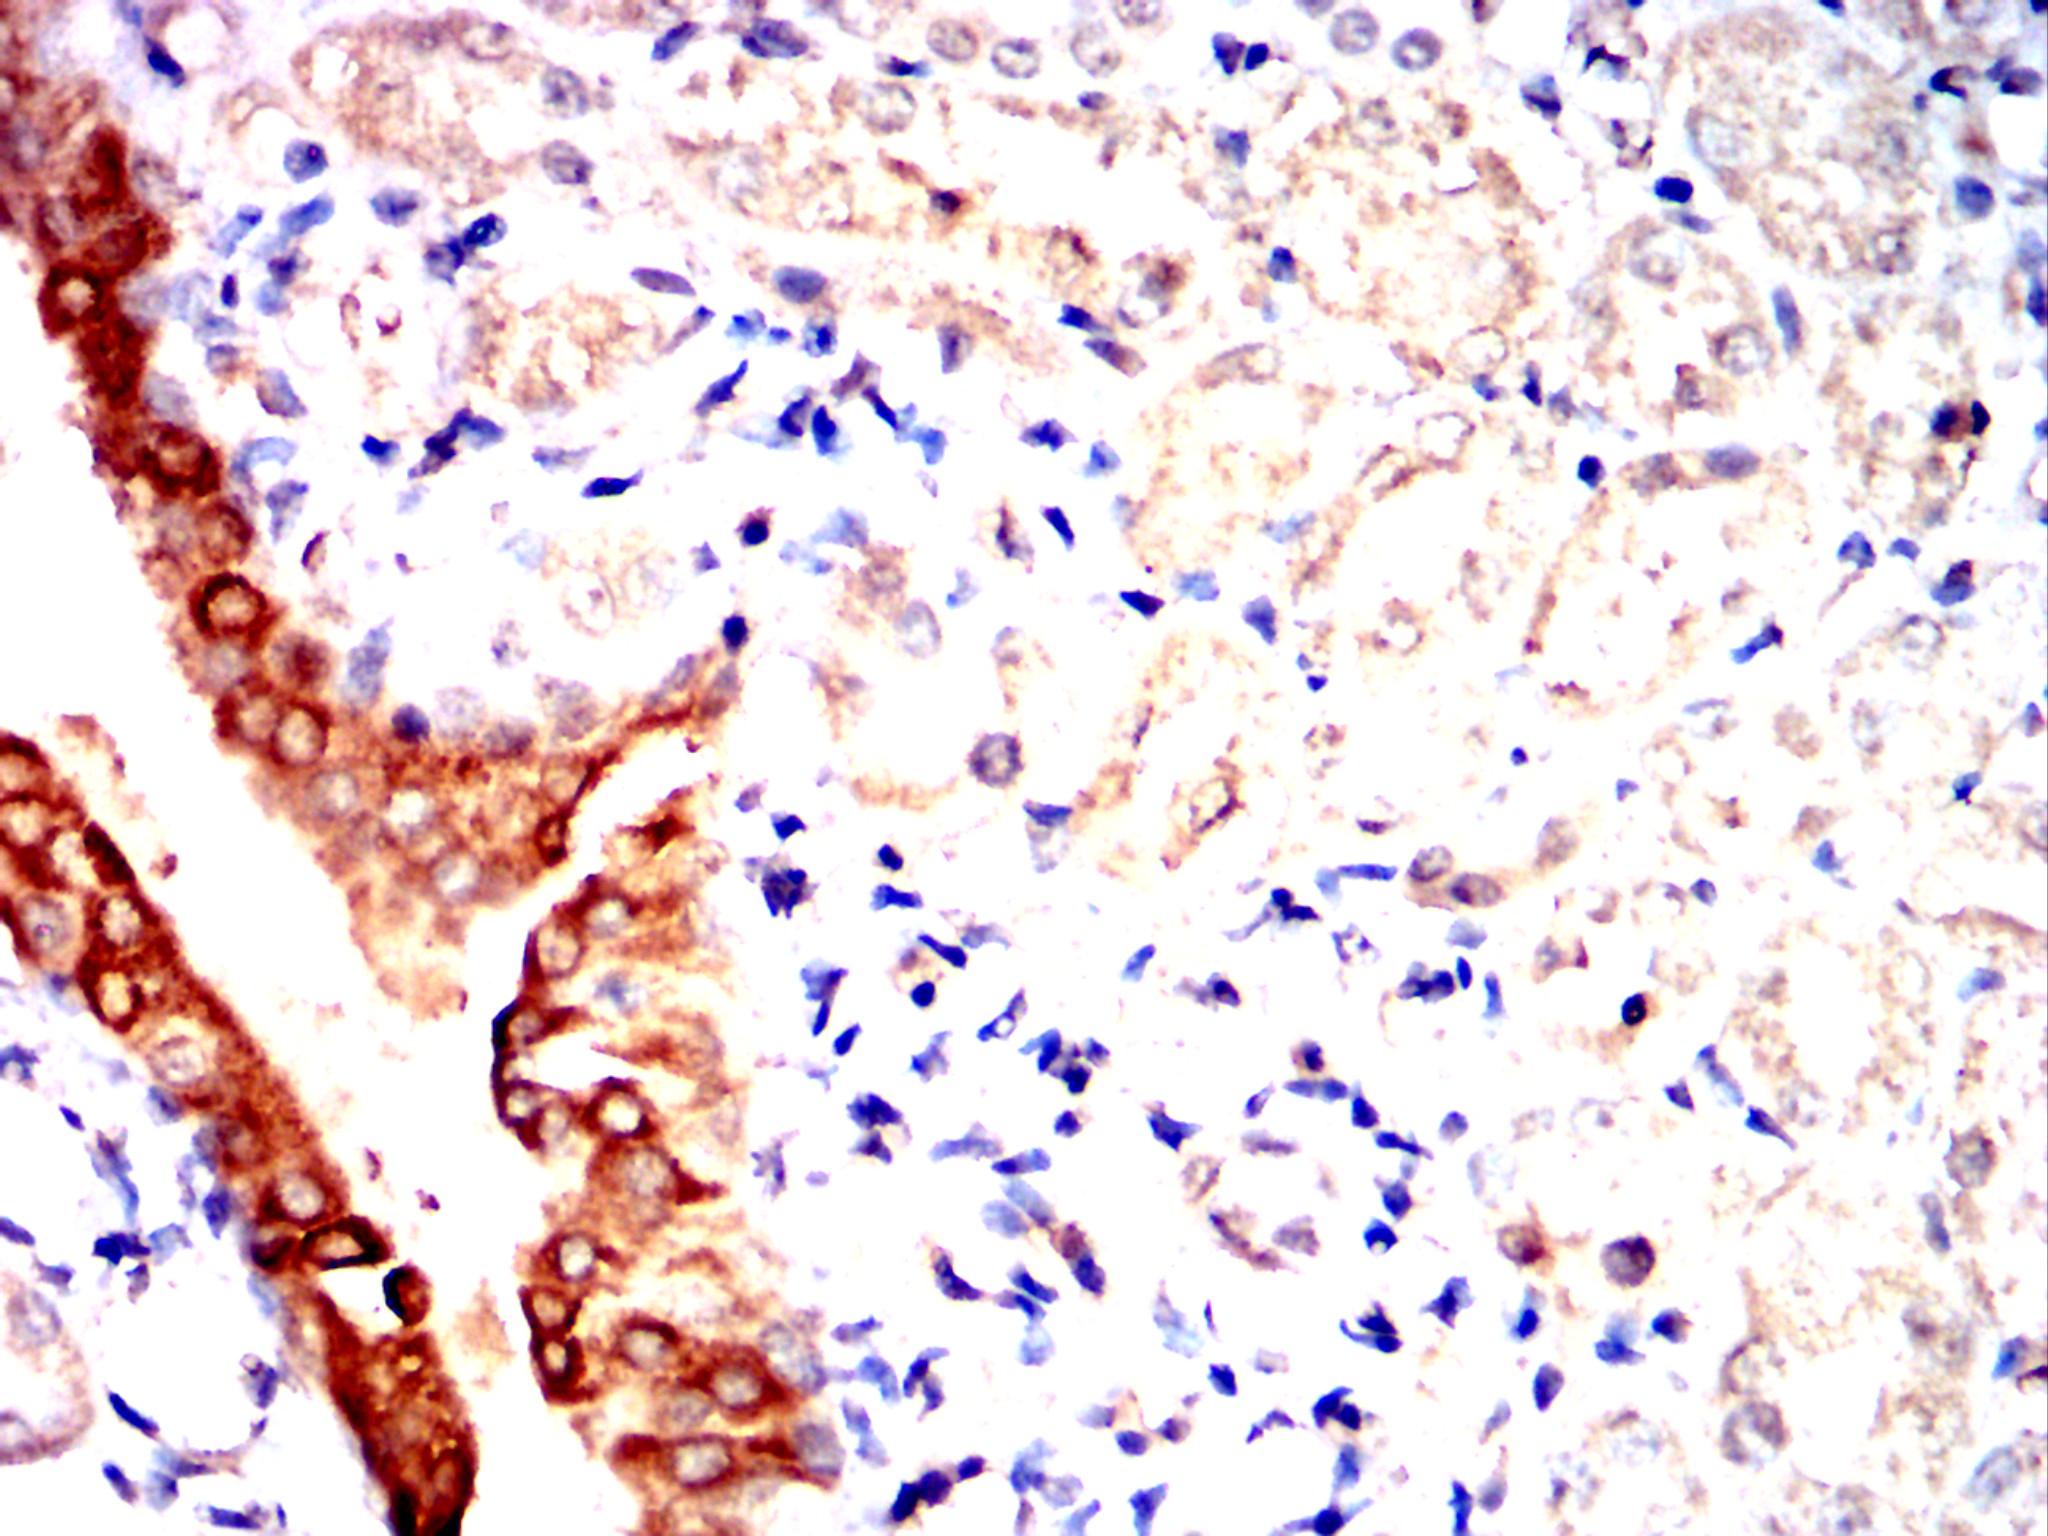

Immunohistochemical analysis of paraffin-embedded human stomach cancer tissues using PRKAA2 mouse mAb with DAB staining.

-

Immunohistochemical analysis of paraffin-embedded human rectum cancer tissues using PRKAA2 mouse mAb with DAB staining.